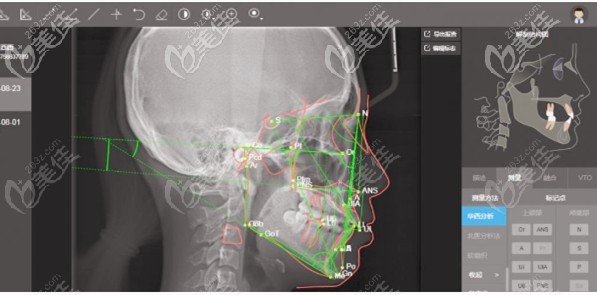

拍一張數(shù)字化口腔CT片,不僅可以清楚看到每個(gè)牙齒的排列位置、牙根傾斜度,連矯正前后外貌的變化也可以從口腔CT上準(zhǔn)確直觀地反映出來。

數(shù)字化口腔CT機(jī)

根據(jù)CT診斷后,可以制定出更好更全面的矯治方案,使矯正后的牙齒整齊、美觀,還可以改變因牙齒所引起的面型問題呢。如:嘴巴前凸、下巴后縮等。

CT診斷口腔效果圖